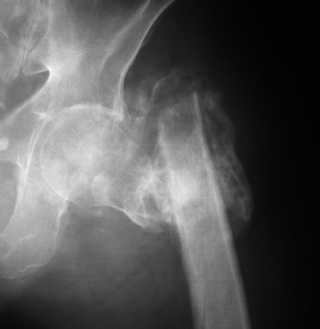

Если снимок справа по хронологии последний, то в тазобедренном сустава наступил анкилоз. Это хороший плюс костной ткани для постановки чашки эндопротеза, но отсутствие сохранения биомеханической оси бедренной кости ставит под вопрос благоприятный вариант усановки ножки эндопротеза.... Учитывая выполненную остеотомию, не считаю выполнение скелетного вытяжения лишенным смысла, для восстановления оси конечности с последующим, возможно, индивидуальным эндопротезированием.

Очень признателен Вам за ответ, но позвольте мне не согласиться с Вами. Я бы пока не делал вывод о анкилозировании тазобедренного сустава. На рентгеновских снимках, да и по данным компьютерной томографии (а этот метод один из самых современных и информативных), хорошо прослеживается постоянной ширины щель между головкой бедренной кости и вертлужной впадины. Кроме того, несложно увидеть разницу "шеечно-диафизарного угла" до и после выполнения тракции в аппарате. Хотя, Алексей, даже если я и прав, это не сильно облегчает нашу задачу.